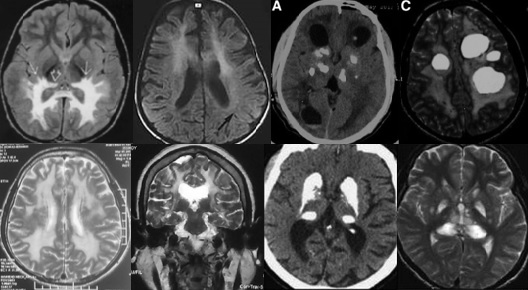

重要申明:以下每个部分会配磁共振图片,因疾病和影像之间存在同病异象、同像异病,为避免误导,图片不标注疾病,请各自鉴赏,另其中有部分图片来源于网络,有疑问可与本人联系。

一、M—metabolism代谢性

代谢性脑病的原因很多,包括氨基酸、有机酸、脂肪酸、糖等代谢异常,以及线粒体功能障碍等,导致高氨血症、低血糖、酸中毒和能量缺乏,引起脑功能障碍。我们在临床上看到的有缺血缺氧性脑病、低血糖致白质脑病、肝性脑病、肾性脑病、Wernicke脑病、线粒体脑病等。中枢神经系统受累的病灶在磁共振上可出现各种表现。

I--inflammation,炎症

脱髓鞘,多发性硬化(MS)、视神经脊髓炎(NMO)、急性播散性脑脊髓炎(ADEM)、MOG相关性脱髓鞘病变、自身免疫性脑炎、CNS血管炎、神经系统结节病、Susac's Syndrome、Clippers’综合症、桥本氏脑病等。还有如急性、亚急性的放疗损伤等。

D--degeneration,变性

如脑梗塞或脑出血等疾病后华勒变性、ALS的锥体束变性等。脑白质疏松症等。